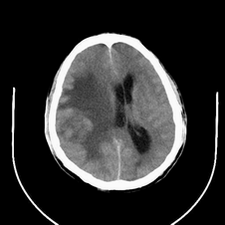

标题: CT25808:男,48岁,头痛多年,近段时间头痛加重伴步态不稳 [打印本页]

标题: CT25808:男,48岁,头痛多年,近段时间头痛加重伴步态不稳

平扫:右颞顶叶病灶呈等低密度伴大面积水肿,脑室受压变形。增强:病灶显著强化。考虑淋巴瘤或黑色素瘤。